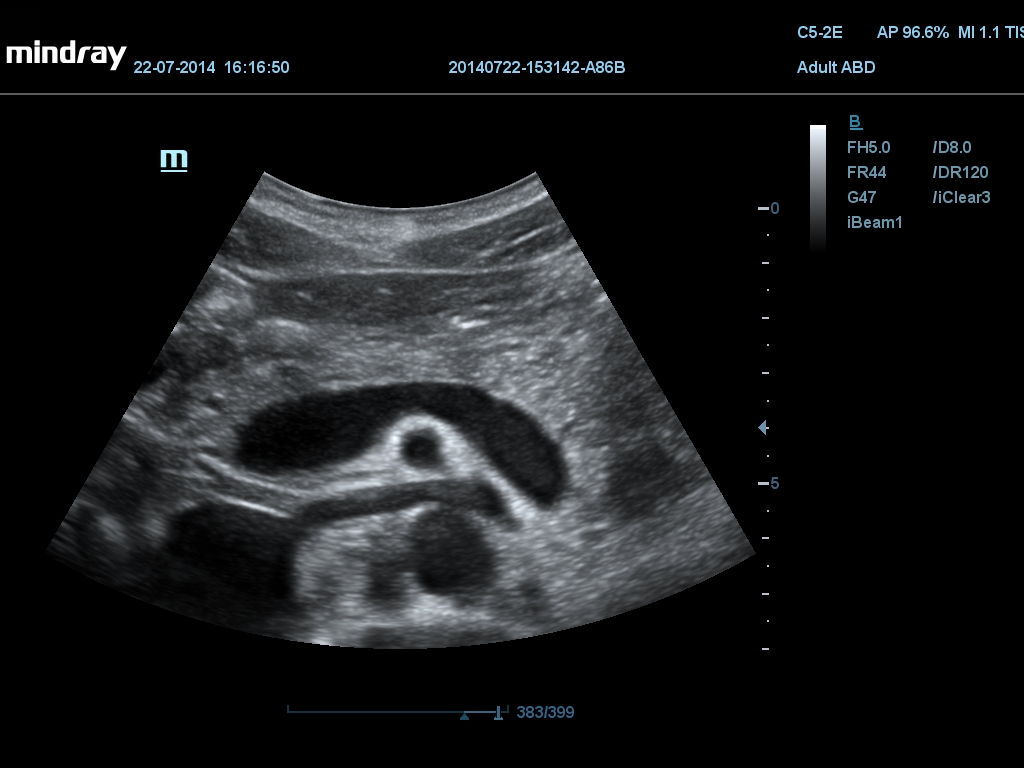

Auto IMT Автоматическая детекция и вычисление толщины комплекса интима-медиа сонной артерии. Опция Auto IMT позволяет получить точную и эффективную оценку состояния стенки сонной артерии.